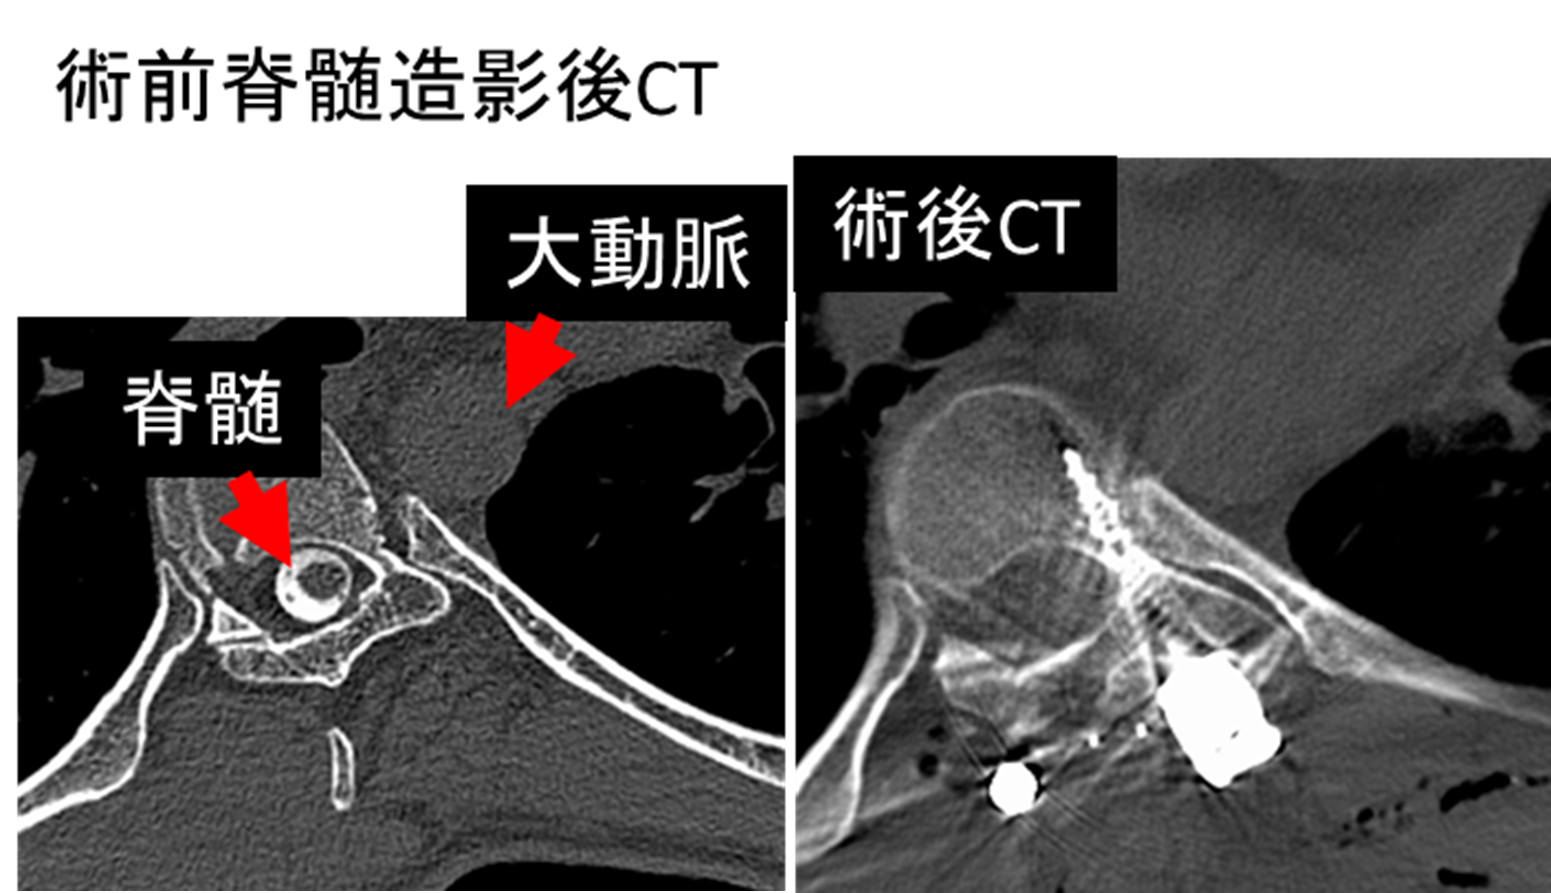

両下肢の脱力による歩行障害に対し脳外科医師

と協力し手術を行っています。術後しびれは残存

していますが、独歩可能です。